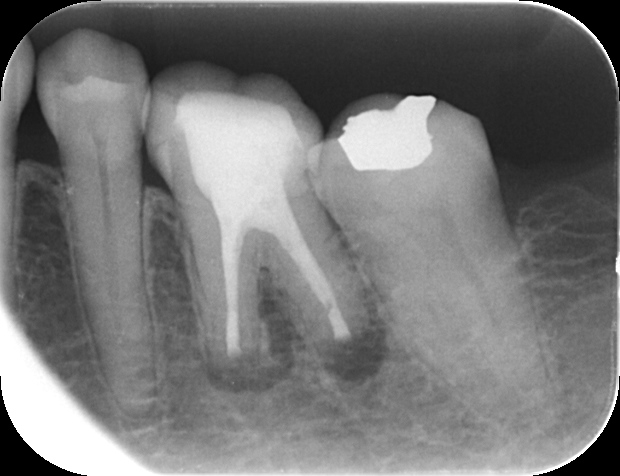

症例 再根管治療後の外科的歯内療法 2025.11.12 【背景】 ・60代女性。 他院で処置するも治らず、専門医による根管治療を希望し来院 外科的歯内療法の可能性を説明し、通法通り処置後、セラミックにて修復 その後、2年ほど経過し、根尖に病変を認めた為、外科的歯内療法へ移行し、 1年経過後のレントゲン写真にて治癒確認 歯内療法完了後 外科的歯内療法直後 1年経過時のレントゲン 【総評】 処置前の診査診断にて、治療の成功率や、外科的歯内療法の必要性について、必ず説明していますが、 一定期間が過ぎてしまうと忘れてしまう患者様は一定数いらっしゃいます セラミック修復した歯を壊す必要がなく、また、抜歯からインプラントへ移行する可能性を減らすことができるため、 難易度は高い処置ですが、専門医で対応することの意義は大きいと感じる症例をご紹介しました 根管治療でお困りの方や、クリニックの関係者の方は、ご紹介フォームからお気軽にお問い合わせください この記事のタイトルとURLをコピーする